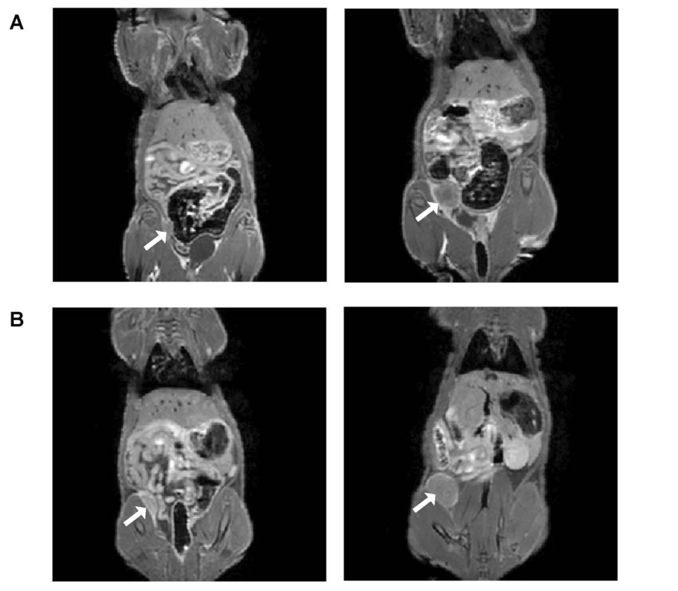

Fig. 1 Cell inoculation under ultrasound image guidance.1, 2

Fig. 2 In-vivo gadolinium contrast-enhanced magnetic resonance imaging (MRI) of orthotopic breast tumors in nude rats at 3 Tesla.1, 2